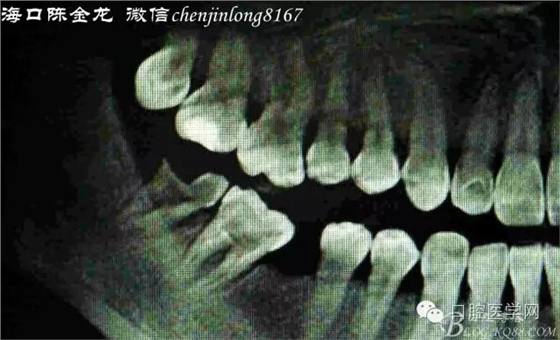

曲面片觀察